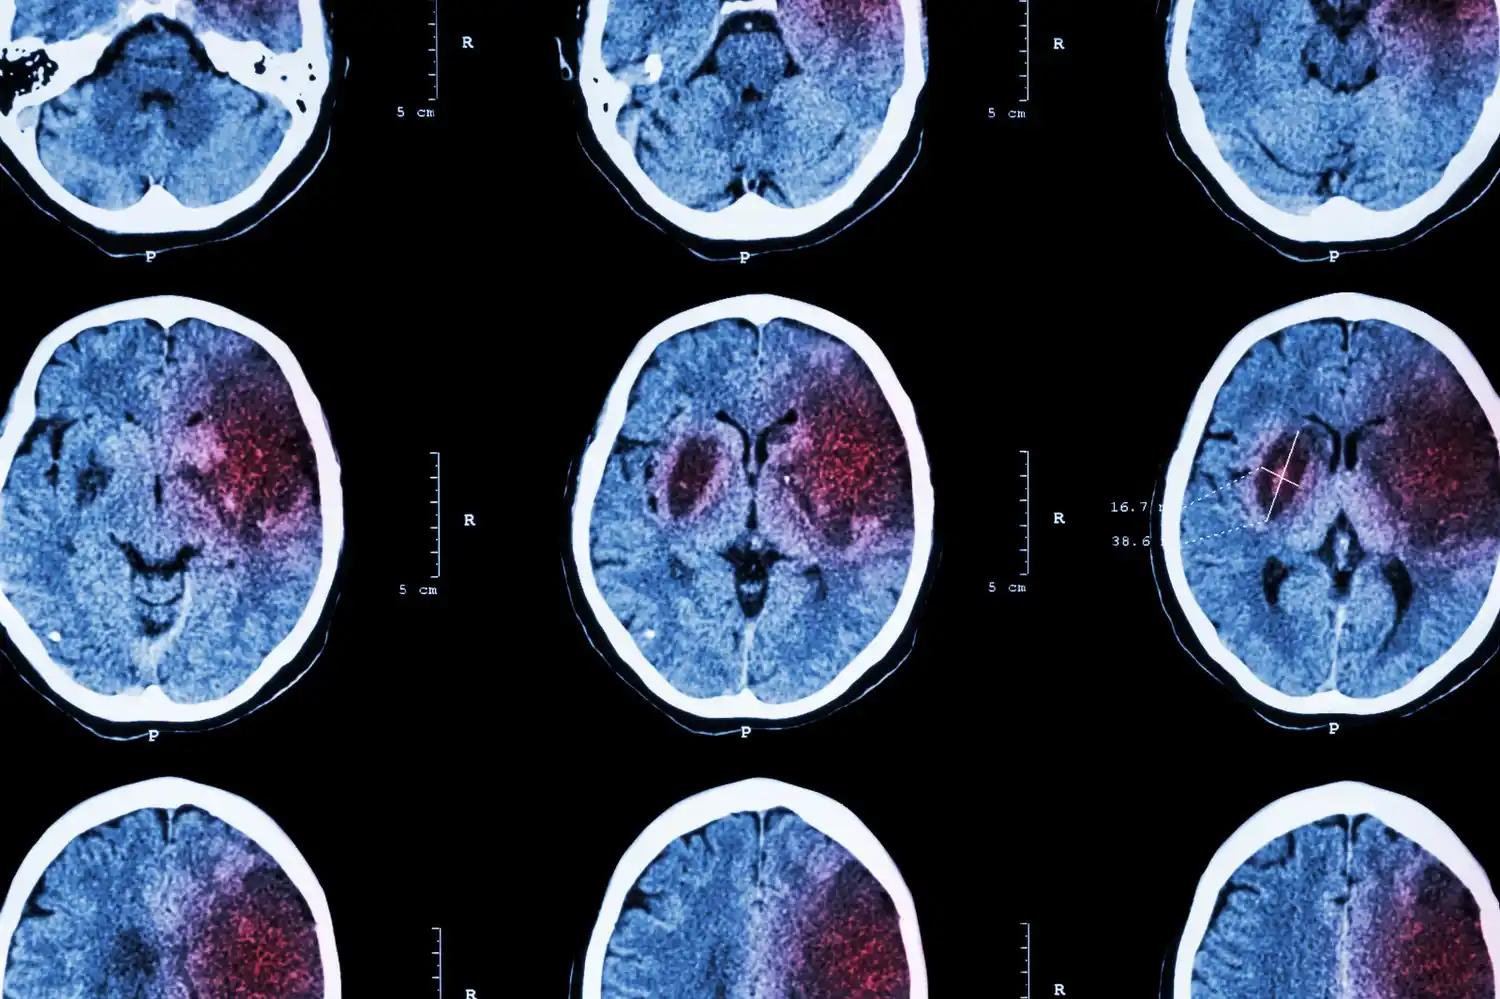

La profesional aclaró que existen dos tipos principales de ACV: el isquémico y el hemorrágico.

“El isquémico se produce cuando se tapa una arteria y deja sin sangre una zona del cerebro, lo que lleva a la muerte de ese tejido. El hemorrágico, en cambio, ocurre cuando se rompe una arteria y hay sangrado dentro del cerebro”.

La prevalencia es mayor en los ACV isquémicos —representan el 80%— y, aunque tienen una mayor tasa de sobrevivir, muchas veces dejan secuelas importantes. “Los ACV hemorrágicos, aunque menos frecuentes, suelen tener mayor mortalidad. Sin embargo, quienes sobreviven muchas veces presentan menos secuelas”, explicó la doctora.